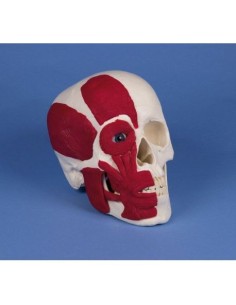

3B Scientific - Mini-modèle anatomique du crâne, en 3 parties A18/15

Crâne classique transparent, séparable en 3 parties, modèle anatomique 3B Scientific A20/T

3B scientifique, enseignement de luxe crâne BONElike™A283

Du crâne en 22 parties à verrouillage magnétique aux modèles de colonne vertébrale, des modèles d'articulation aux modèles de cœur, chaque pièce de notre collection est conçue pour une immersion totale dans l'étude de l'anatomie humaine. Nos modèles, réalisés à partir de scans d'os réels, garantissent une expérience tactile authentique et une fidélité de poids presque identique aux originaux.

Indispensables aux étudiants comme aux professionnels, nos modèles anatomiques sont des outils pédagogiques qui permettent d'observer les structures anatomiques avec précision, en évitant les dissections ou les études invasives. Ils sont également utiles pour expliquer les pathologies aux patients, ce qui rend la communication plus efficace et permet de gagner un temps précieux.